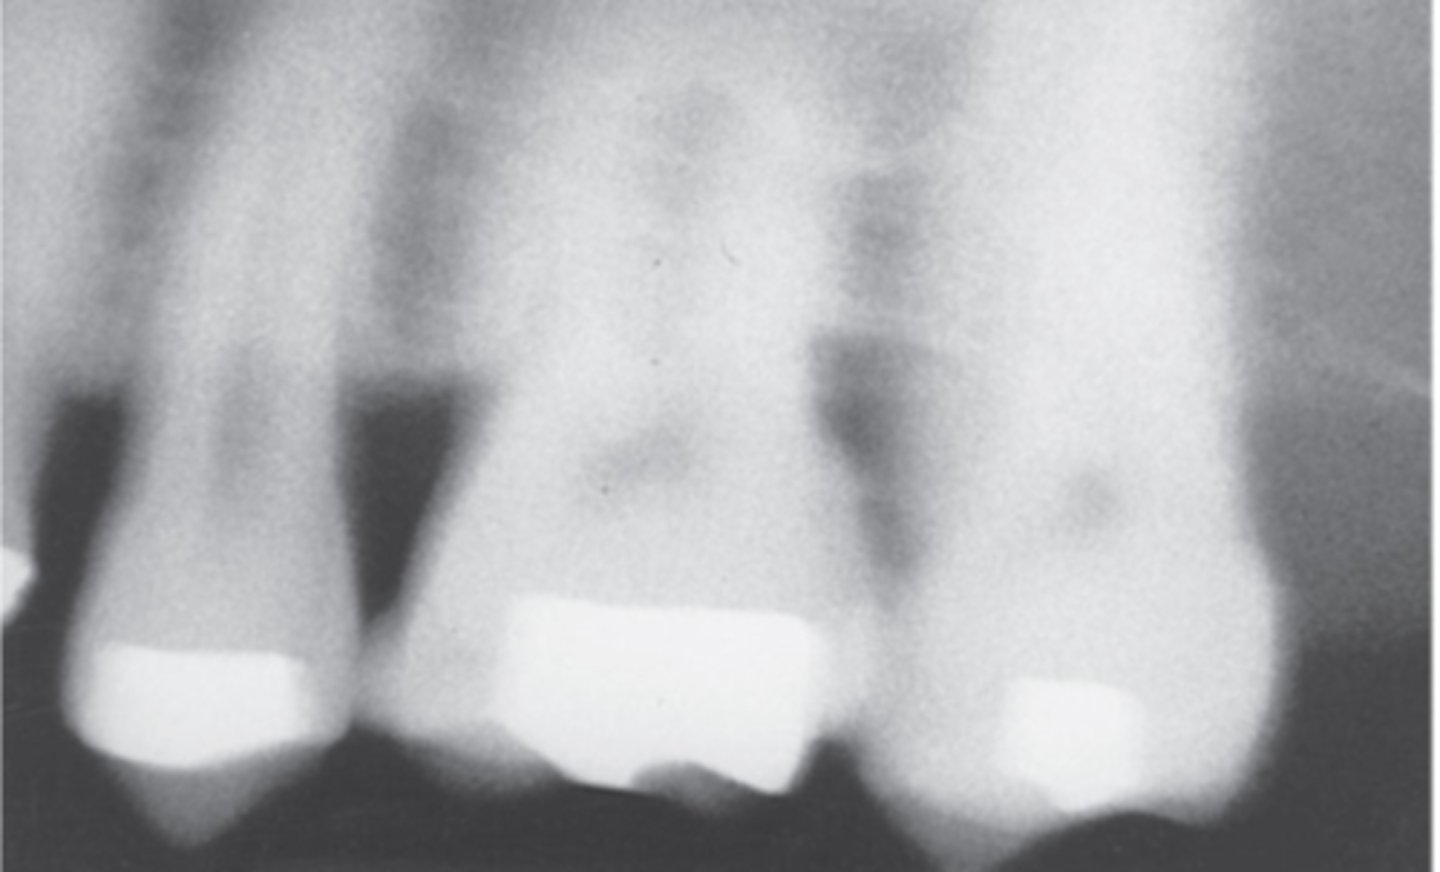

Foreshortened Images

The vertical angulation was excessive, or too steep, and as a result images are shorter than the actual teeth

<p>The vertical angulation was excessive, or too steep, and as a result images are shorter than the actual teeth</p>